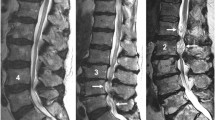

Load and activity changes of the spine typically cause symptoms of nerve root compression in subjects with spinal stenosis. Protrusion of the intervertebral disc has been regarded as the main cause of the compression. The objective was to determine the changes in the size of the lumbar spinal canal and especially those caused by the ligamentum flavum and the disc during loaded MRI. For this purpose an interventional clinical study on consecutive patients was made. The lumbar spines in 24 supine patients were examined with MRI: first without any external load and then with an axial load corresponding to half the body weight. The effect of the load was determined through the cross-sectional areas of the spinal canal and the ligamentum flavum, the thickness of ligamentum flavum, the posterior bulge of the disc and the intervertebral angle. External load decreased the size of the spinal canal. Bulging of the ligamentum flavum contributed to between 50 and 85% of the spinal canal narrowing. It was concluded that the ligamentum flavum, not the disc had a dominating role for the load induced narrowing of the lumbar spinal canal, a finding that can improve the understanding of the patho-physiology in spinal stenosis.

The characteristic symptoms in spinal stenosis, neurogenic claudication, are believed to be caused by an encroachment of the nerve roots of the cauda equina. The symptoms typically develop or are worsened during walking or in certain postures both assumed to initiate or aggravate the nerve root constriction. Since the diagnostic MRI or CT examinations of the spine, in suspected spinal stenosis, usually are performed in the supine patient, the loading conditions differ from those known to elicit the symptoms in the stenotic spine. To achieve more realistic loading conditions during imaging of the spine special devices have been developed [1, 2, 16, 17]. By applying an axial spinal load corresponding to 50% of the body weight during the MRI or CT examinations a further constriction of the cauda was noted in quite many patients with suspected spinal stenosis [1, 16]. The contribution of different structures, e.g. the disc or the ligamentum flavum to the load induced constriction of the spinal canal and the dural sac was never determined [2, 16, 17].

Load induced changes of the spinal canal’s cross-sectional area (SCcsa)

The average cross-sectional area of the spinal canal, SCcsa (Fig. 1) in the unloaded spines decreased with an average of 23 mm2 at the L3/L4 level when exposed to axial loading. The corresponding decrease at the L4/L5 level was 17 mm2 (Table 5).

Ligamentum flavum’s contribution to the load induced changes in the cross-sectional area, SCcsa of the spinal canal

Loading of spine reduced the available space inside the spinal canal at the L3/L4 level with 23 mm2 and at the L4/L5 level with 17 mm2. The ligamentum flavum’s share of this reduction of the available space inside the canal was 8.9 + 2.7 = 11.6 mm2 for the right and left side at the L3/L4 level. At the L4/L5 level the corresponding figures were 12.9 + 1.6 = 14.5 mm2 (Table 4). Consequently, the yellow ligament was responsible for 50% (11.6/23 × 100) of the reduction of available space within the spinal canal at the L3/L4 level and as much as 85% (14.5/17 × 100) at the L4/L5 level.

This study confirmed what several other studies already have shown, that the available space within the lumbar spinal canal varies depending on the loading conditions of the spine [2, 12, 17]. By quantifying separately each structure’s contribution to the reduction of the size of the spinal canal in the unloaded and loaded spines (Fig. 1), it was evident that the yellow ligament’s share in that process has been underestimated. The finding that ligamentum flavum contributed to between 50 and 85% of the load induced narrowing of the spinal canal made it the most significant and “dynamic structure” determining most of the load induced changes of the available space within the spinal canal. Consequently, load induced symptoms due to cauda equina encroachment seemed more likely to be caused by bulging of the ligamentum flavum than protrusion of the disc. The load induced bulging of the ligamentum flavum was reflected both by the measures of its thickness and cross-sectional area. The changes were closely related but for the purpose of determining the intrusion of the ligament into the spinal canal only the area measure was appropriate.

Ligamentum flavum caused more of the narrowing of the lumbar spinal canal than the disc in axially loaded spines. The bulging ligament represented from 50 to 85% of the reduction in size of the spinal canal when in the supine patient the load was changed to simulate sitting or upright standing. For that reason a load induced bulging of the ligamentum flavum seemed more likely to cause also the classical load and motion-related symptoms due to cauda equina encroachment than a protruding disc.